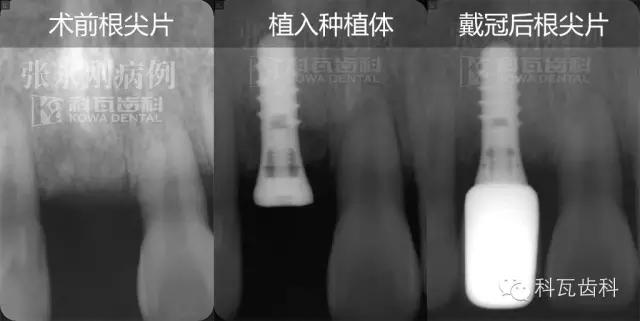

術(shù)前牙根片顯示:雖然缺牙時間較長,但是缺牙部位牙槽骨高度密度均可

2013年3月2日,采用微創(chuàng)種植牙技術(shù),為缺牙部位植入一顆ITI4.1/10RNSP種植體,手術(shù)順利,術(shù)后佩戴臨時牙冠,不影響正常的咀嚼以及美觀度。

5、2個月后,佩戴全瓷冠

佩戴全瓷冠后,修復(fù)后的牙齒和自然牙渾然一體,幾乎無法辨別,自然、美觀、和諧??腿藵M意。